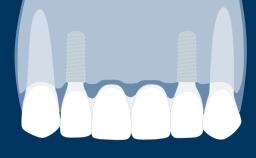

Fixed and removable prosthodontic implant therapy for restoration of the edentulous maxilla is both complex and challenging. Careful assessment and planning is needed in each individual case to explore whether a fixed or a removable solution will be the more suitable to satisfy the patient’s preference for optimal esthetics, phonetics, comfort and function. This Learning Pathway explores the prosthodontically driven treatment planning based on structured assessment, considered diagnosis and practical application in clinical case examples.

• recognize the importance of a prosthodontically driven plan and of planning implant configurations and placement accordingly

Edentulous Maxilla Fixed vs. Removable Prosthodontics Planning Principles Prosthodontic Planning & Procedures Prosthodontic Planning & Procedures